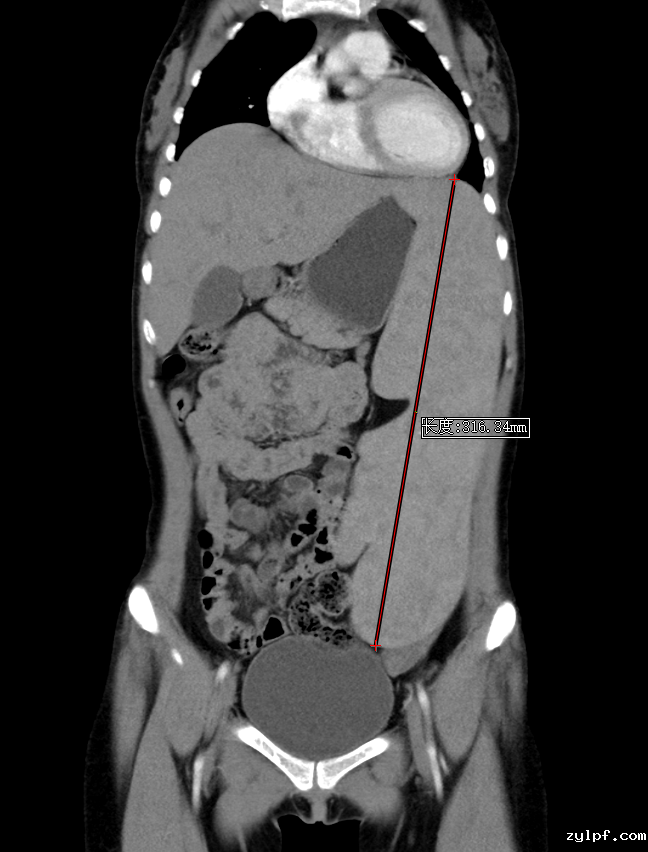

胸腹部增强CT:1.脾脏重度肿大,最大径线超过30cm,脾静脉明显增粗,考虑门脉高压。2.心室及大血管血液密度减低,考虑贫血。

CT示脾脏重度肿大,最大径线超过30cm